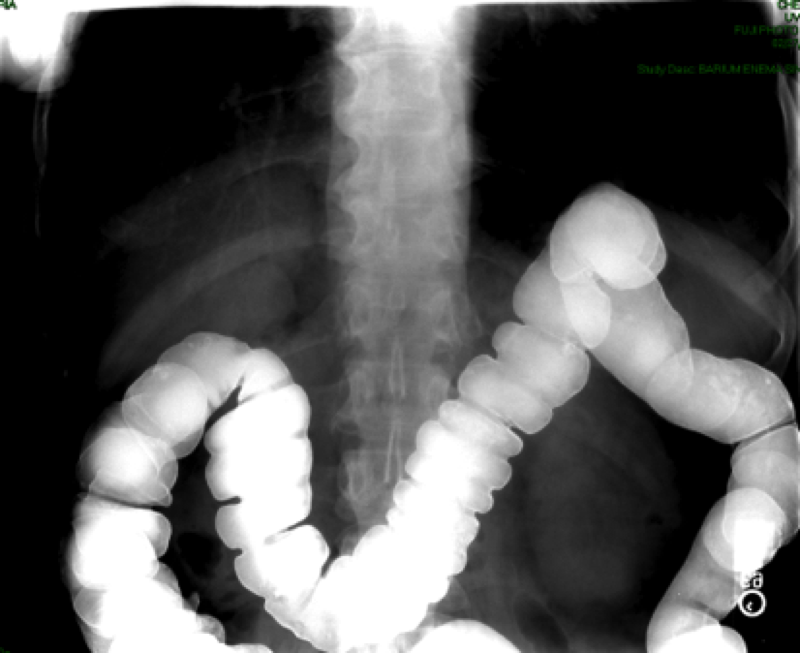

- AP or PA position to include the entire colon. PA is preferable if the patient can tolerate (it may be necessary to take more than one image to image the whole colon)

(key image 12)

(key image 13).